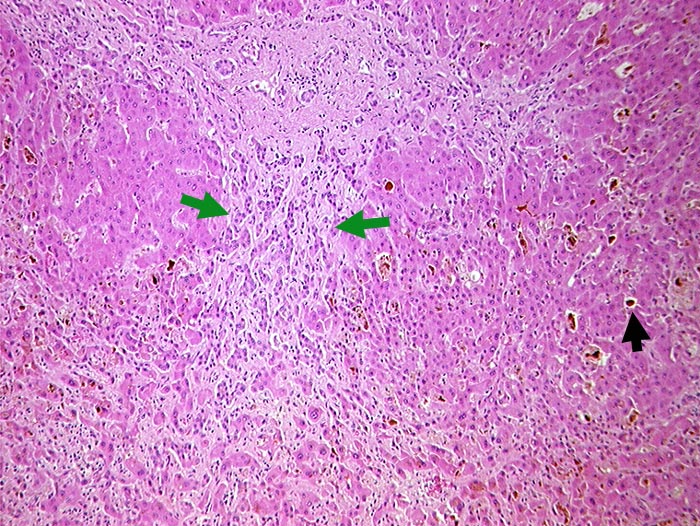

► Gallezylinder in erweiterten interzellulären Canaliculi (Gallethromben). ► Ductulusproliferationen im leicht fibrosierten Portalfeld.

Gallenblasenkarzinom. Kompression des Ductus choledochus durch Lymphknotenmetastasen im Leberhilus.